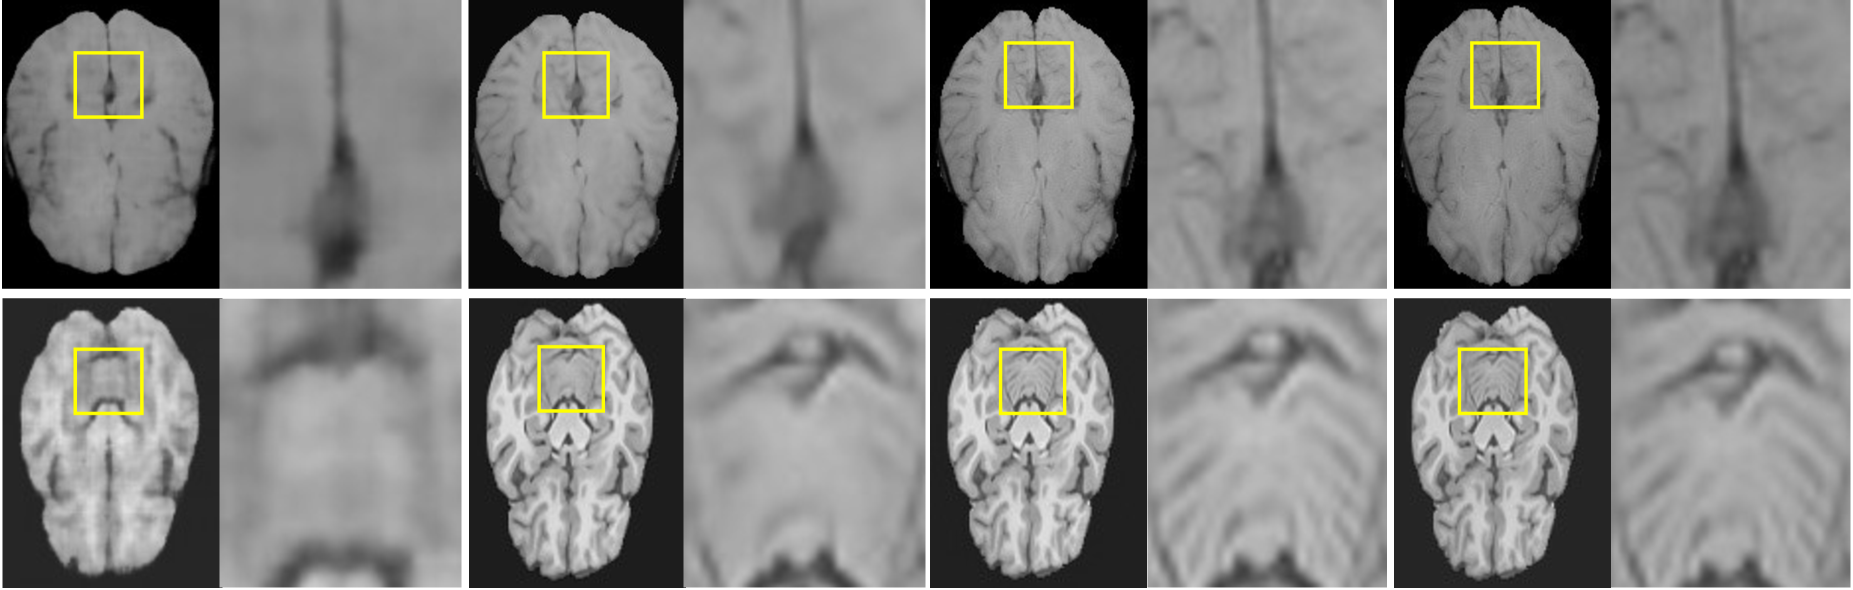

We have detailed the results obtained using two up-sampling scales on two 3D MRI datasets in Tab.I, and all quantitative results are the average of the evaluation metrics of 50 patients in the two datasets. As shown in the Tab.I, our method essentially outperforms the baseline methods for MR image SR tasks. In addition, we visualize the MR image SR results of the proposed method and other baseline methods on the BraTS 2019 [29] and MSSEG 2016 [28] datasets in Fig.2. Compared to the baseline methods, the proposed method more accurately recovers detailed textures and complex structures in HR image, achieving better visual fidelity and reducing holes and blur.